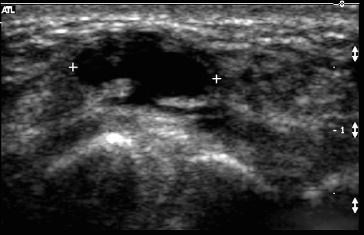

Transverse and longitudinal views of

the mediastinum of the testis